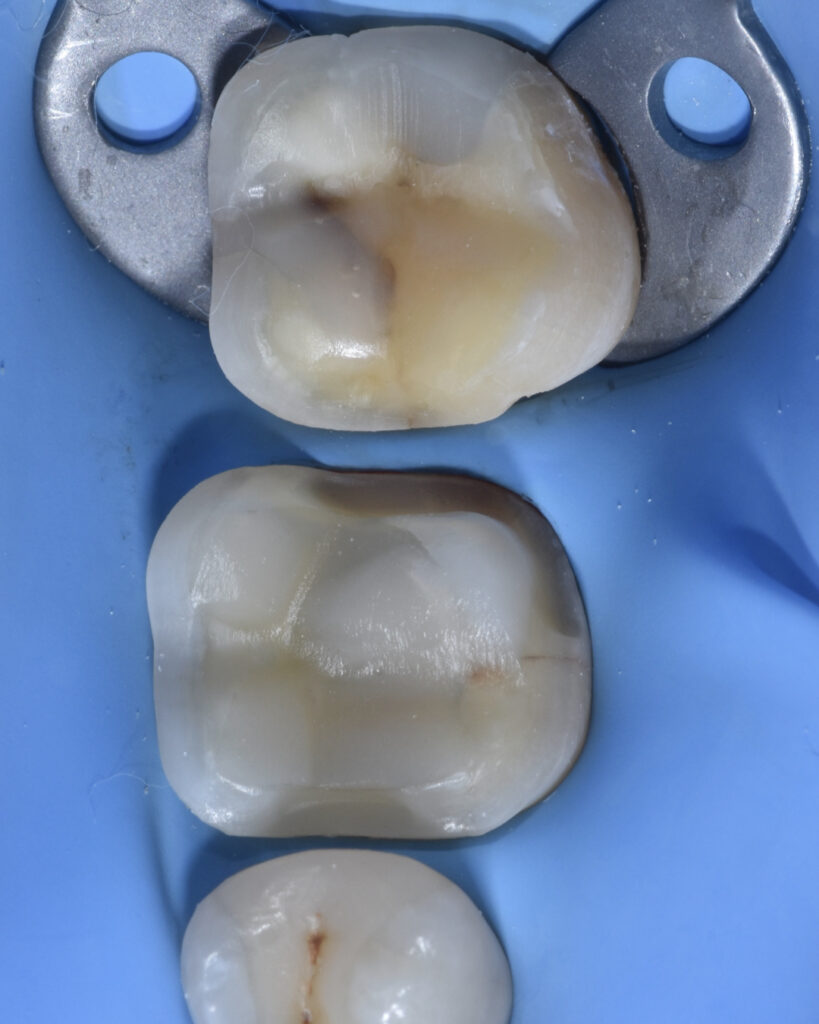

The prosthetic restorations were treated as follows:

• 9% hydrofluoric acid for 10 seconds

• 37% orthophosphoric acid for 90 seconds

• Silane application

• Universal adhesive

Adhesive cementation was performed using preheated composite resin.